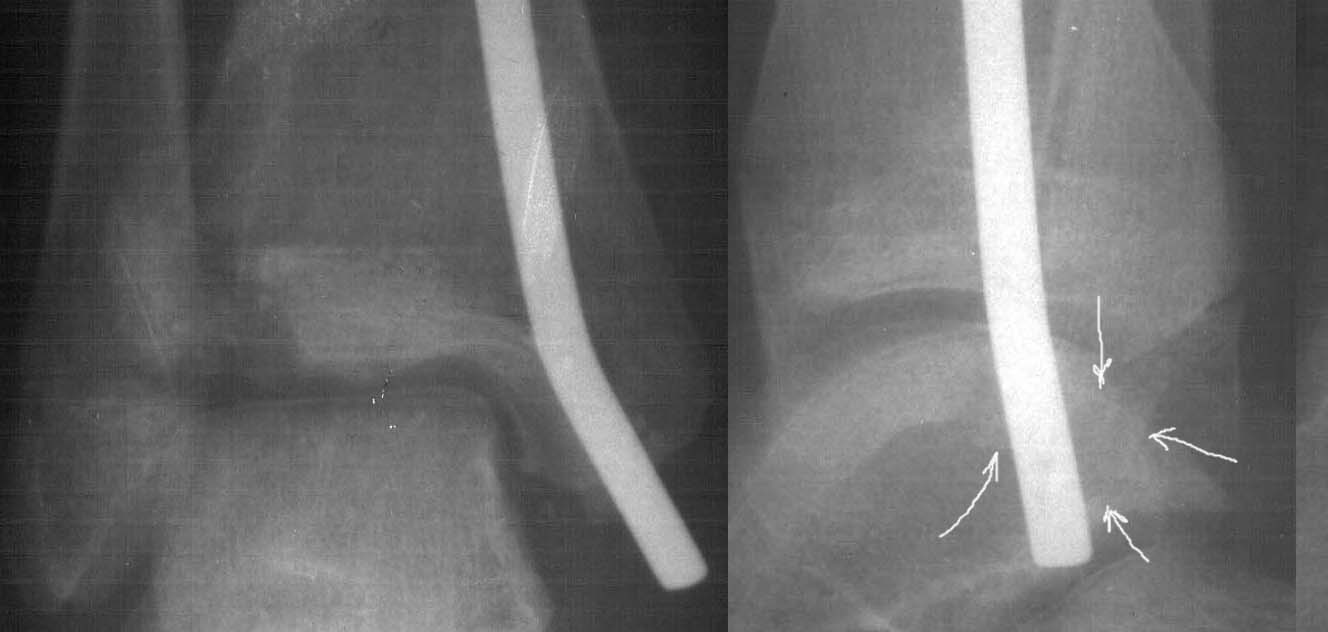

Девочка 14 лет полтора года назад оперирована в детской больнице по поводу спирального перелома костей голени (снимок 1)- выполнен закрытый остеосинтез стержнем Богданова, введенным ретроградно с медиальной стороны (снимок 2). Фиксатор после сращения удален

(см. снимки 3 и 4, после удаления, для сравнения со здоровой стороной, фас - стоя с нагрузкой на обе ноги). В настоящее время беспокоят боль и отеки в области голеностопного сустава при нагрузках, после ходьбы. В покое и ночью боли нет.Амплитуда движений в голеностопном суставе практически полная. Имеется заметная боковая нестабильность, т.е. несостоятельность дельтовидной связки и межберцоого синдесмоза. Складывается впечатление, что при остеосинтезе был отколот и смещен в сторону сустава костный фрагмент позади внутренней лодыжки, увеличилось смещение отломка заднего края, что привело к столь ранним проявлениям деформирующего артроза. Встает вопрос - что делать сейчас?Артодез - наверно, рано. Ревизию сустава, моделирующую резекцию?Пластику связок? Что-то еще? Заранее спасибо.

умаю дельтовидная связка и дистальный тибио-фибулярный синдесмоз не повреждены. При операции гвоздь вколочен внутрь сустава между медиальным

малеолярным отростком и талюсом так, что отломил и оттеснил медиально ту часть медиального маллеола, который обеспечивает медиальную стенку "ворот" (мортис) голеностопа. Сейчас при ходьбе талюс сублюксирует в медиальном

направлении. От этого боли и отёки при ходьбе.

Мне в тоже время совершенно ясно видно по той же КТ, по 4 срезам, расположенным в центре и вверху пленки, что перелома внутренней лодыжки не было, в следующем собщении я приложу увеличенный фрагмент томограммы. А к этому письму прилагаю увеличеный фрагмент послеоперационной рентгенограммы, где выделил отколотый фрагмент

позади внутренней лодыжки. И он, как я вижу, находится между стержнем и тараном. А перелома внутренней лодыжки, и тем более смещения, IMHO

не определяется.

К сожалению на последних присланных срезах КТ нет более низкого, через таран, среза, который был на прежнем майле. На XR я попытался показать

стержень внутри сустава и то как он раскрывает пространство между тараном и мед. малеолом.